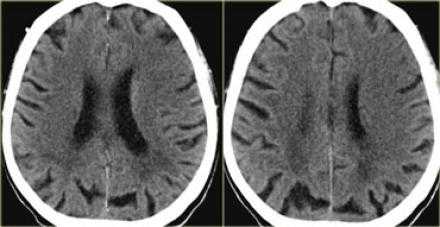

Обратите внимание на изображение и предположите, где патология. После продолжите чтение. Вывод:

Есть некоторая гиподенсность и отек в левой лобной доли со старостью борозд в сравнении с контр-латеральной стороной. Далее DWI снимки того же пациента. После просмотра DWI нет сомнения, что это инфаркт. Именно поэтому DWI называют инсульт последовательностью.

Когда мы сравниваем результаты на T2WI и DWI во времени, мы заметим следующее: В острой фазе T2WI норма, но со временем зона инфаркта станет гиперинтенсивной. Гиперинтенсивность на T2WI достигает своего максимума между 7 и 30 дней. После этого сигнал начинает угасать. На DWI гиперинтенсивная область в острой фазе, а затем становится более интенсивной с максимумом на 7 дней. На DWI у пациента с инфарктом головного мозга визуализируется гиперинтенсивная область примерно на 3 недели после начала заболевания (при инфаркте спинного мозга на DWI визуализируется гиперинтенсивная область на одну неделю!). На ADC будет сигнал низкой интенсивности с минимальной интенсивностью в первые 24 часа, после сигнал будет увеличиваться в интенсивности и, наконец, становится максимально интенсивным в хроническую стадию.